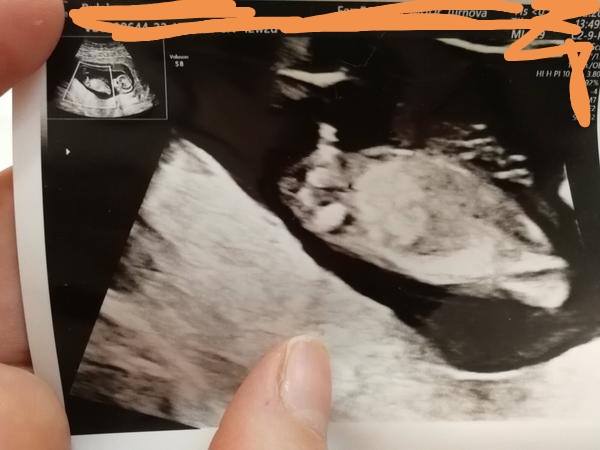

vedeli by ste mi pomôcť zmenšiť nedočkavosť... čo to bude? 😇

Zdá sa mi, že to čo trčí tak dohora nie je pipík. 🙂 Keďže vľavo hore to skôr vyzerá na nohu :]

z takej fotky ťažko povedať s úplnou istotou. Čisto teoreticky by to mohol byť chlapček. Bábätko je ale podľa fotky ešte maličké, takže skôr pôjde o inú časť tela.